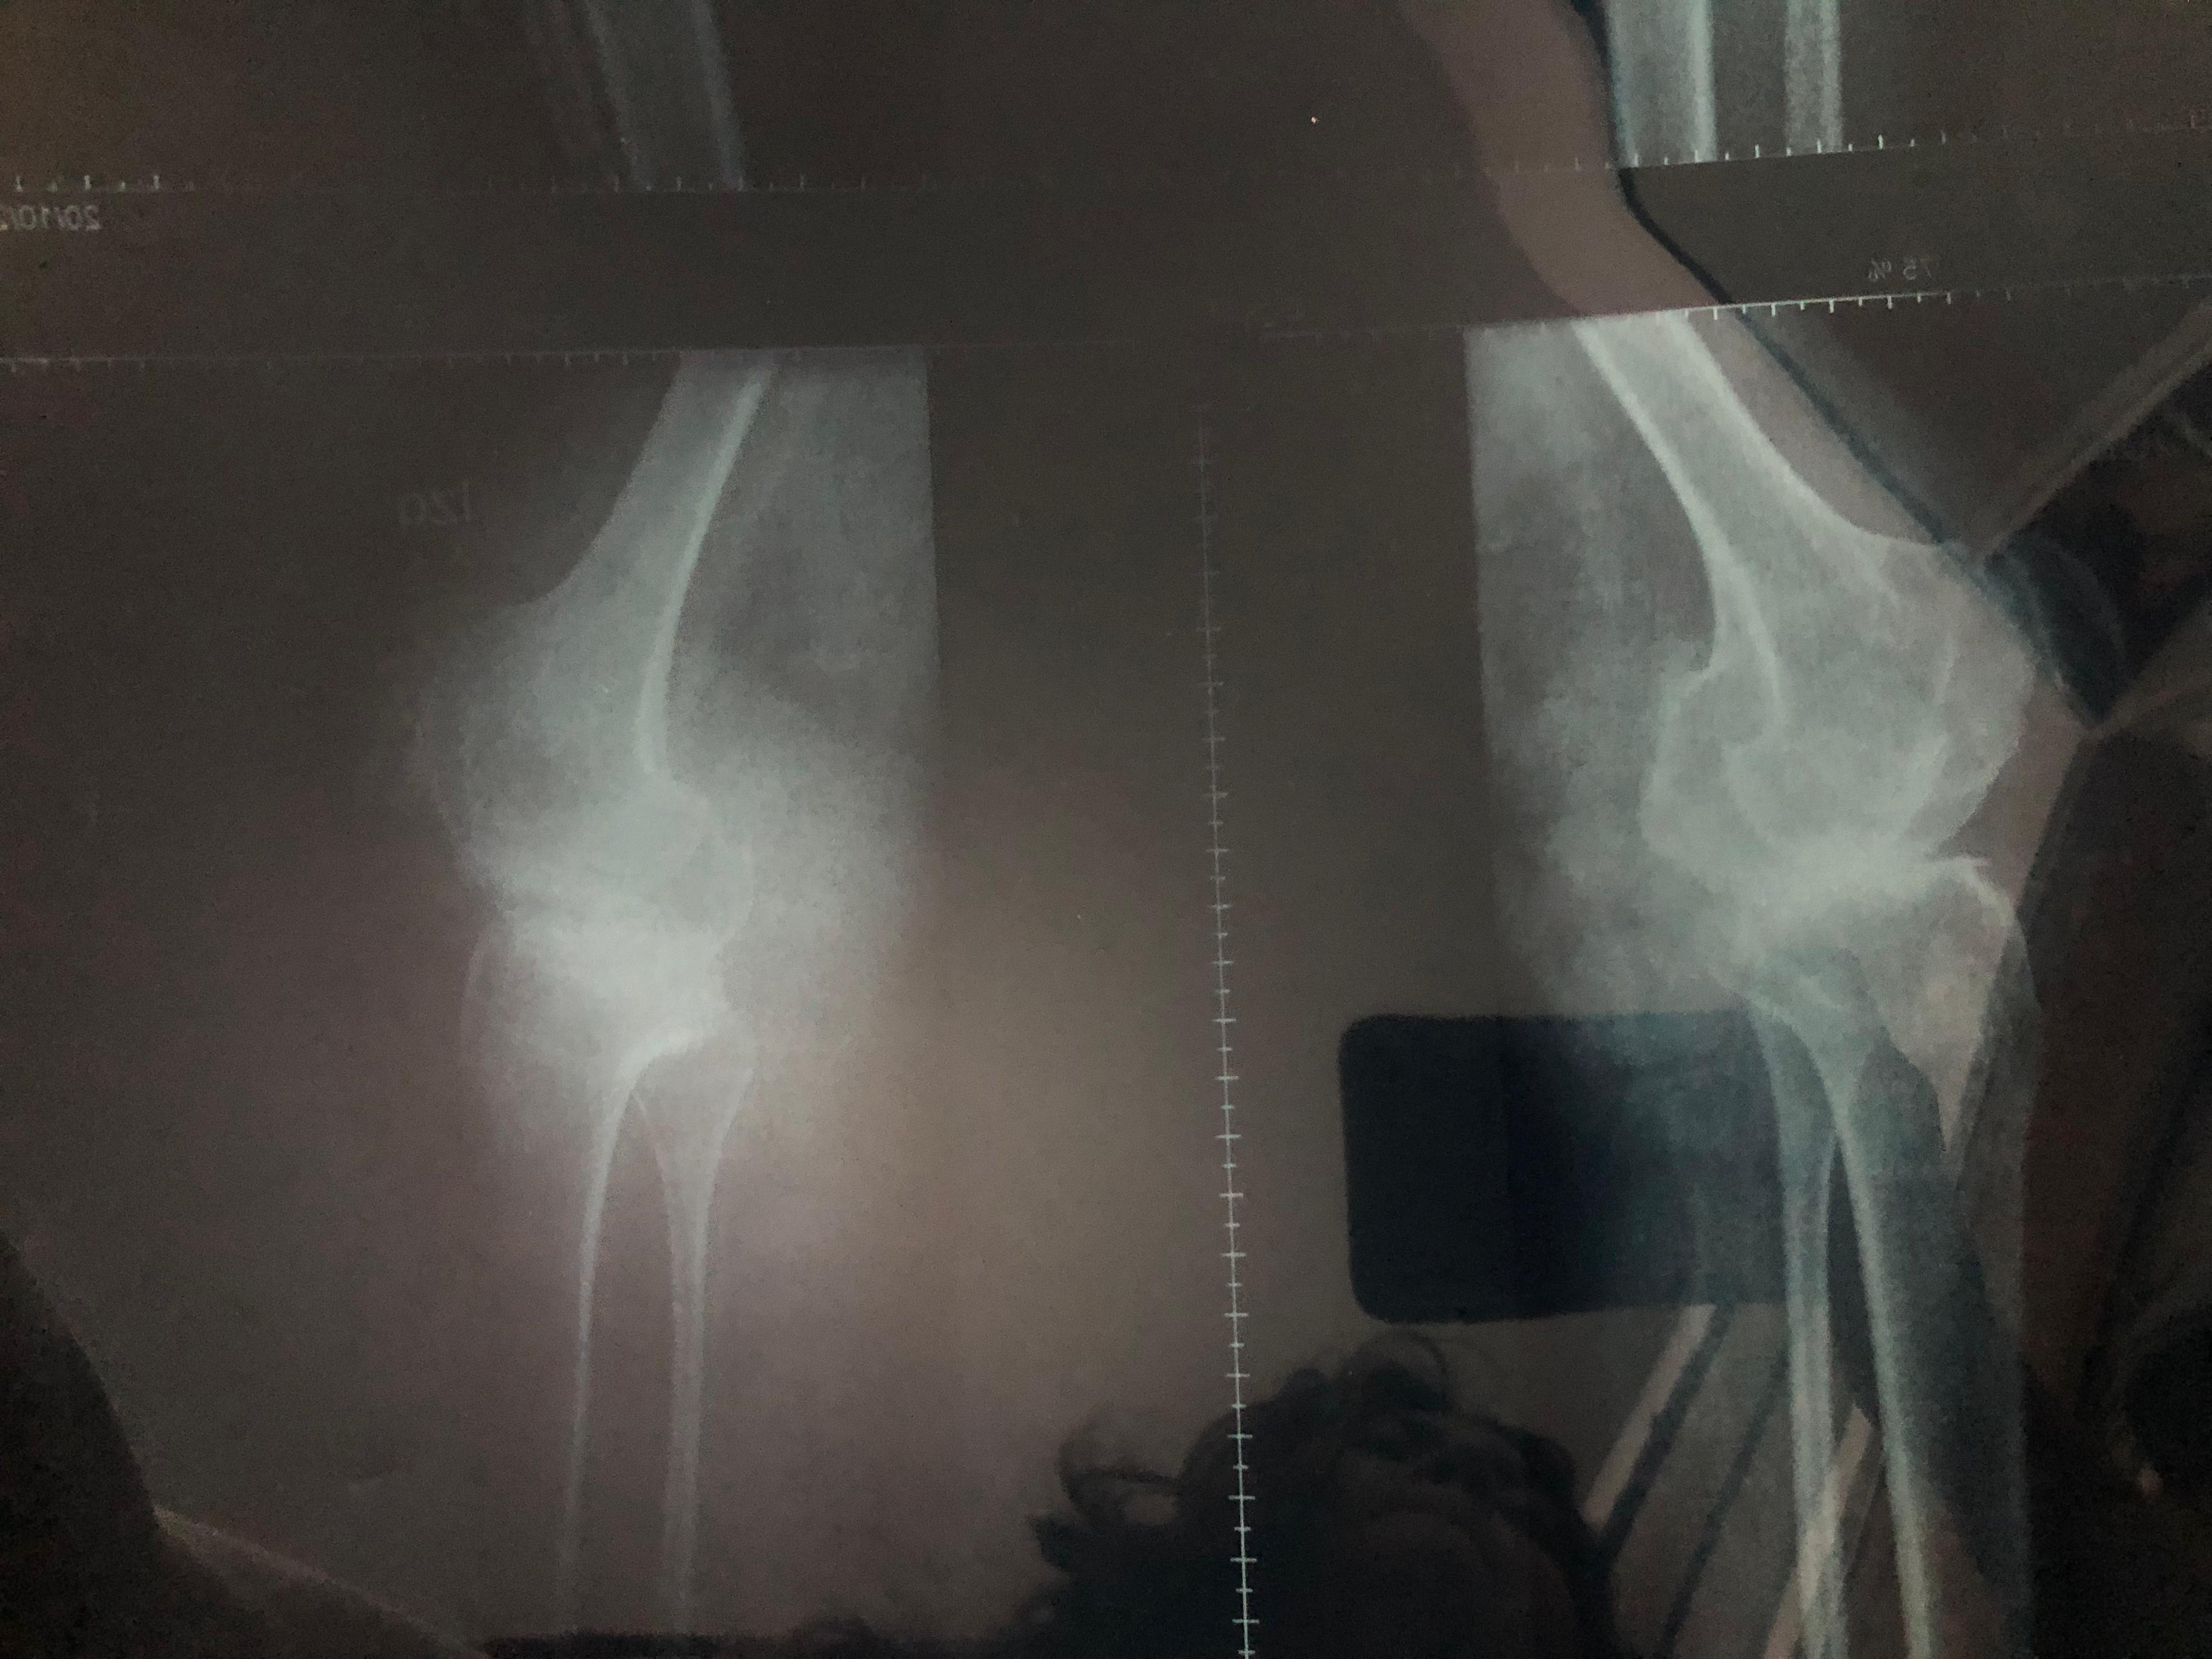

Soy Venezolana y nací con artritis Reumatoidea Juvenil, actualmente tengo 33 años, mi enfermedad a evolucionado a artritis Reumatoidea gotosa y en muchas partes ya tengo artrosis.

Hoy necesito prótesis en ambas caderas y ambas rodillas, las cuales son de reemplazo total.

Me fui de Venezuela a Argentina porque me dijeron que acá podrían ayudarme y aunque pueden operarme, no me pueden dar las prótesis adecuadas para mí condición de salud y edad. Las que me recomiendan son las de mejor calidad, durabilidad y por ende las más costosas!!. (Bioimpianti italiana ip magnam o Artrotek maxx americana. Para reemplazo total de rodillas y caderas)